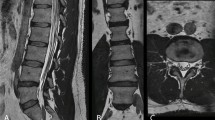

Thirty-five patients (mean age 58 ± 19, 26 female) were evaluated. 3D DLRecon demonstrated statistically significant higher median image quality score (2.0/2) when compared to SOC 3D (1.0/2, p < 0.001), 2D axial (1.0/2, p < 0.001), and 2D sagittal sequences (1.0/2, p value < 0.001). κ ranges (and 95% CI) for foraminal stenosis were 0.55–0.76 (0.32–0.86) for 3D DLRecon, 0.56–0.73 (0.35–0.84) for SOC 3D, and 0.58–0.71 (0.33–0.84) for 2D. Mean κ (and 95% CI) for central stenosis at L4-5 were 0.98 (0.96–0.99), 0.97 (0.95–0.99), and 0.98 (0.96–0.99) for 3D DLRecon, 3D SOC and 2D, respectively.

DLRecon 3D T2w-FSE L-spine MRI demonstrated higher image quality and similar interobserver agreement for graded variables of interest when compared to 3D SOC and 2D imaging.